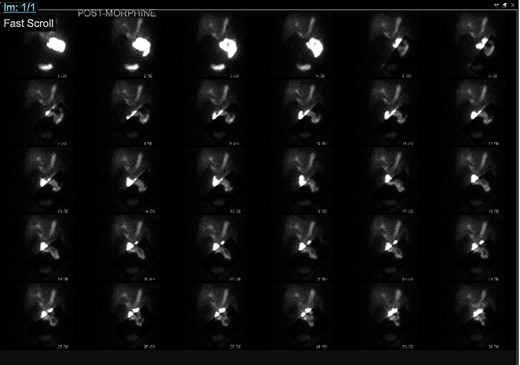

The patient returned to the clinic 2 years later due to continued pain, located over the epigastric, right upper and right lower aspects of her abdomen. She underwent the HIDA scan with 5-mCi Choletec, which demonstrated a non-visualized gallbladder throughout the entire study even with the administration of 3.6-mg morphine, which were consistent with chronic cholecystitis. At her subsequent clinic visit, she continued to report right upper quadrant pain, which now radiated to the right side of her back worse after fatty food intake and with associated nausea. Because of her HIDA scan finding of cholecystitis and her continued symptoms, she was scheduled for an outpatient laparoscopic cholecystectomy.

Gallbladder agenesis is a rare anomaly in which an individual is born without a gallbladder. This phenomenon affects <0.1% of the population with only 400 cases documented in medical literature to this day [2, 3]. This anomaly is discovered incidentally during workups for symptoms consisting of gallbladder pathology as seen in our patient. Initial work up for a gallbladder pathology includes a right upper quadrant ultrasound and, in this patient, it showed a collapsed gallbladder around gallstones, as seen in Fig. 4. This pointed to a diagnosis of cholecystitis. A further look with a HIDA scan confirmed this diagnosis as it showed the absence of radiotracer entering the gallbladder even after the administration of morphine, seen in Figs 5 and 6. A non-visualized gallbladder typically occurs due a gallstone obstructing the passage of the radiotracer entering the gallbladder [4]. Gallbladder agenesis could cause this radiographic finding as well, however, this anomaly was low in our differential as the initial ultrasound showed a collapsed gallbladder and the patient’s absence of other medical conditions associated with gallbladder agenesis, such as Klippel–Feil syndrome, horseshoe kidney, malrotation of the gut or aberrant left pulmonary artery, none of which were suspected in our patient seen on examination and radiographically [1]. The normal location of the gallbladder is located on the undersurface of the liver, aligning with the intrahepatic line that separates the right and left hepatic lobe. There was no sign of this organ once the liver was elevated, seen in Fig. 1. The likely cause of this patient’s chronic right sided abdominal pain were the multiple abdominal adhesions, which were lysed.

HIDA scan showing normal extraction of radiotracer into the biliary tree with non-visualization of the gallbladder, post morphine.